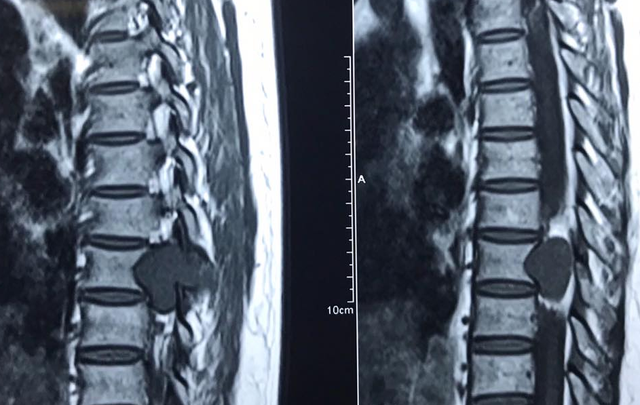

Tê bì tay chân là tình trạng phổ biến, gặp ở nhiều đối tượng, không phụ thuộc vào độ tuổi. Tê bì tay chân có thể là biểu hiện sinh lý bình thường của cơ thể nhưng cũng có thể là dấu hiệu của nhiều bệnh lý nguy hiểm, trong đó có u cột sống.

Đau, tê bì, yếu tay chân là dấu hiệu đầu tiên của bệnh nhưng nhiều người thường chủ quan nghĩ tuổi còn trẻ lại làm công việc văn phòng ngồi nhiều nên chị chỉ đi xoa bóp, bấm huyệt, không đi khám, chỉ đến khi đau nhiều hoặc tê liệt không vận động mới đi khám thì bệnh đã ở giai đoạn muộn.

U cột sống nếu không được phát hiện và điều trị thì khối u sẽ gây chèn ép làm tổn thương thần kinh đến mức không hồi phục, để lại di chứng nặng nề như yếu liệt, đại tiểu tiện mất kiểm soát,…